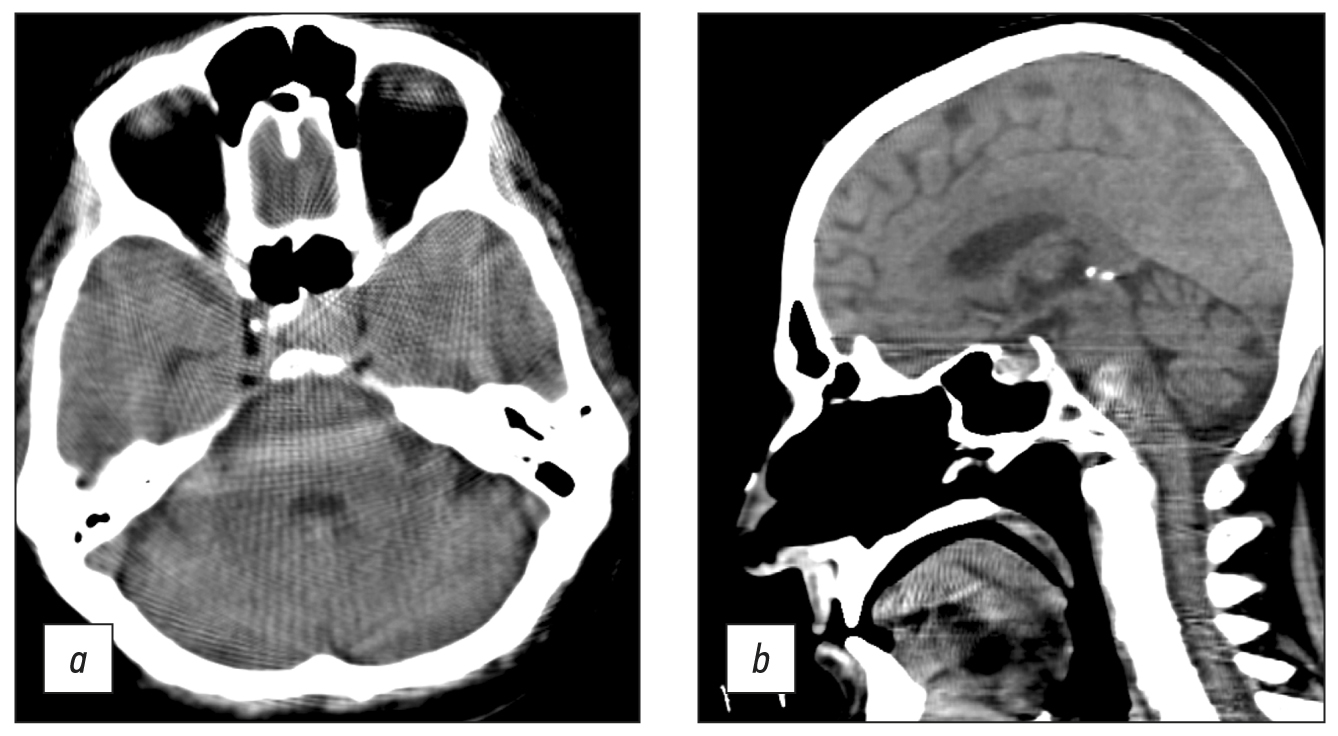

Brain CT was used to diagnose acute cerebrovascular accident, intracranial hematomas, brain tumors, and traumatic skull injuries (Fig. 7).

Fig. 7. Axial computed tomographic images of the brain: (a) reconstruction of a 3-mm low-density area at the anterior horn of the left lateral ventricle, in the periventricular, subcortical direction (CT image of subacute cerebrovascular accident of the left middle cerebral artery), and (b) a 1-mm site of subarachnoid hemorrhage with blood breakthrough into the ventricular system (vicarious hydrocephalus).

Windmill artifacts (Fig. 8a) were mixed with strike artifacts and helical scanning [5], and artifacts intensified at the level of skull base, where significant beam hardening and scattering artifacts occurred (Fig. 8, b). Therefore, subtentorial brain areas were challenging to assess.

Fig. 8. Axial (a) and sagittal (b) computed tomographic images of the head in the region of the posterior cranial fossa and base of skull showed windmill, strike, beam hardening, and scattering artifacts. Area of bone structures and the posterior fossa is hard to evaluate.